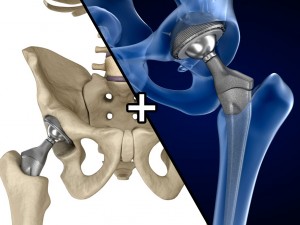

spinal fixation system - titanium bracket. human spine, spinal cord, sacrum and fixation system medically accurate high quality 3d model.

spine fixation spinal cord screw surgery system anatomy backbone bone brace bracer bracket column disc paralyze titanium treatment vertebra이 아이템에 대한 코멘트 없음.